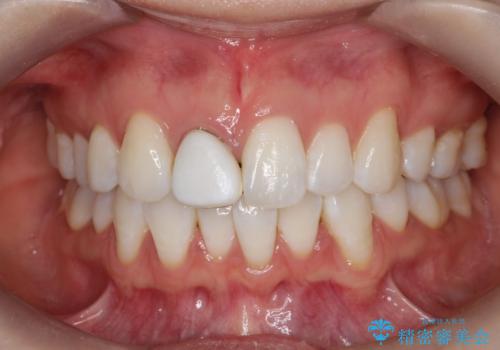

- 患者様は、前歯の被せ物の形や色が不自然で気になるというお悩みを抱えて来院されました。

診察の結果、既存の被せ物は古い素材で作られており、周囲の歯との調和が難しいことが分かりました。患者様とカウンセリングを重ね、アライナー矯正で歯列のガタツキを修正後、。より自然で審美的な仕上がりを目指してオールセラミッククラウンでの治療を提案しました。